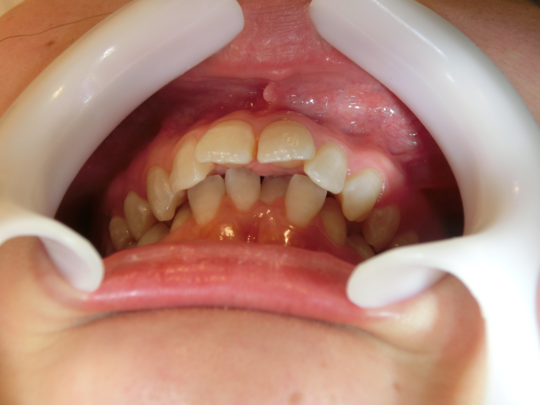

矯正前(上の歯)

矯正前(下の歯)

こちらの患者さまは、あごが小さいために前歯がきれいに並びきらず、「叢生(そうせい)」という前後がデコボコな歯並びでした。矯正後は、きれいに前歯が並んだだけではなく、上下の噛み合せも正しい位置に動き、しっかりと噛めるようになりました。

治療説明 歯科矯正でも目立ちにくい矯正方法です。透明に近いマウスピース型の矯正装置(アライナー)のため、歯に装着しても目立つことなく歯並びを矯正することが出来ます。また、一人ひとりの合わせて矯正装置を作製いたします。

治療期間 11か月

治療費用498000 円

治療の副作用(リスク)歯の動き方には個人差があり、予想された治療期間が延長する可能性があります。治療中は矯正歯科装置をつけるためハミガキを適切に行ってお口の中を常に清潔に保ち、さらに、かかりつけ歯科医に定期的に受診することが大切です。マウスピースの使用状況、定期的な通院など、矯正歯科治療には患者さんの協力が必要であり、それらが治療結果や治療期間に影響します。治療の経過によっては当初予定していた治療計画を変更する可能性があります。保定装置の装着時間が十分確保できない場合、歯並びや、咬み合せの「後戻り」が生じる可能性があります